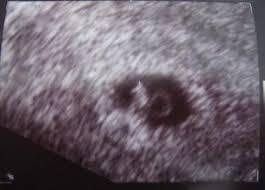

In dieser Fruchthöhle finden sich gelegentlich bereits kleine weißliche Flecken die durch die embryonalen Strukturen hervorgerufen werden. Woche SSW5 Alter 3 Wochen. In der Regel werden Zwillinge bereits bei der ersten Ultraschalluntersuchung entdeckt die etwa in der sechsten Schwangerschaftswoche erfolgt.

Grösse 15-3 mm - so gross wie ein Sesamkorn. Schwangerschaften entstehen - und das ist nun wirklich nicht überraschend neu - nachdem eine Eizelle von einem Samenfaden befruchtet wurde.